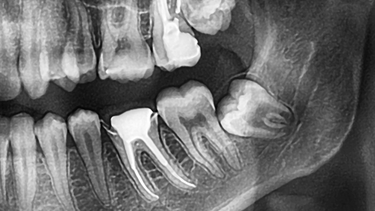

Răng số 8 hay còn được gọi là răng khôn là chiếc răng mọc cuối cùng ở mỗi cung hàm. Thời điểm răng xuất hiện thường vào độ tuổi trưởng thành từ khoảng mười bảy đến hai mươi lăm tuổi. Khi xương hàm đã phát triển hoàn chỉnh và không còn nhiều không gian, răng số 8 dễ bị kẹt trong nướu hoặc xương. Điều này dẫn tới tình trạng răng mọc lệch, mọc ngầm, xoay sai hướng hoặc cắm sâu sát thần kinh.

Nhổ răng số 8 vì vậy thường phức tạp hơn so với răng khác. Nếu chân răng chạm sát ống thần kinh hàm dưới hoặc xoang hàm trên thì trong và sau phẫu thuật dễ xảy ra những biến chứng sau khi nhổ răng số 8. Tuổi của người nhổ càng lớn, vị trí mọc càng sâu, phẫu thuật càng khó và tỉ lệ rủi ro càng tăng.

Do đó trước khi nhổ bác sĩ thường yêu cầu chụp phim để đánh giá rõ tình trạng răng và đưa ra phương án phù hợp. Chuẩn bị tốt ngay từ đầu sẽ góp phần giảm nguy cơ biến chứng.

Có cần chụp phim trước khi nhổ răng số 8 không

Cần thiết vì phim giúp bác sĩ đánh giá chính xác vị trí và hình dạng răng từ đó lựa chọn cách phẫu thuật an toàn.